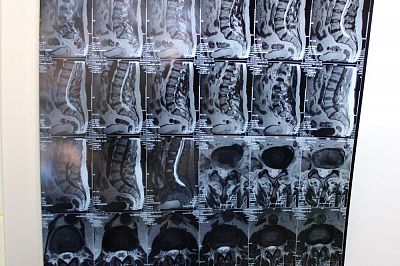

Секвестрированная грыжа позвоночника (секвестр) поясничного отдела - самый тяжелый вариант развития межпозвоночной грыжи позвоночника. Происходит выпадение диска в спинномозговой канал, поражаются нервы и твердая мозговая оболочка.

Чаще всего пациент может точно указать время и место, когда произошла секвестрация - как правило, такая грыжа возникает в момент резких движений (подъема тяжестей, или неловкого поворота, падения). В случае нашего пациента, он как раз занимался перестановкой мебели. В результате мебель осталась переставлена наполовину, а мужчина с сильнейшей болью (до потери сознания) был привезен в больницу.

«Больные с секвестрированной грыжей, как правило, надолго «застывают» в той позе, которая кажется им менее болезненной, - рассказывает врач-нейрохирург высшей квалификационной категории Нина Николаевна Вознесенская. - Чаще всего это поза «на четвереньках», в которой и доставили нашего пациента. Именно в таком положении защемленному нервному корешку становиться чуть легче. Если, конечно, можно так сказать - в подобных ситуациях даже наркотические анальгетики плохо справляются с болью».